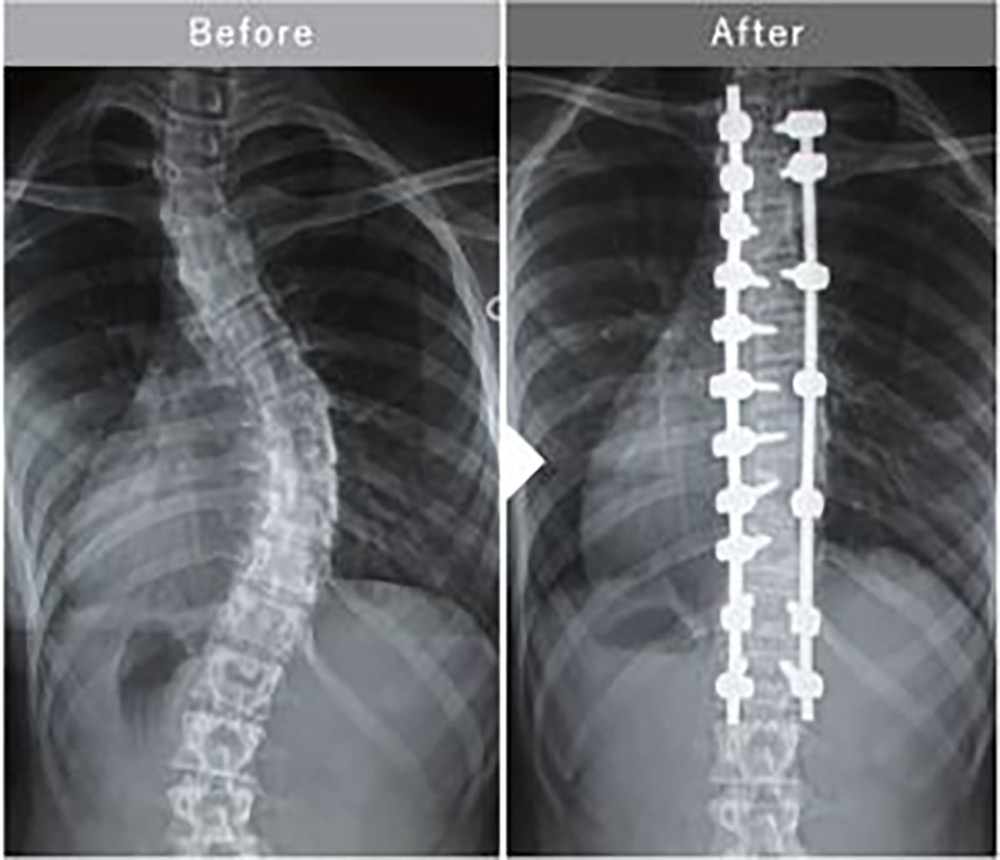

特発性思春期側弯症に対する後方矯正固定術

手術の目的は、脊椎の変形を可及的に矯正した状態で固定し、呼吸機能障害や腰背部痛、容姿や精神的問題などが顕在化してくる重度の側弯への進行を予防することです。一般的にはCobb角が40度以上の側弯が対象になりますが、年齢(骨の成長度)等も加味して、手術の必要性を判断します。

手術が望ましい症例では、いたずらに手術時期を遅らせると変形が進行し手術の範囲が長くなってしまう場合もあり、適切な時期に手術を行うことが望ましいと考えられます。